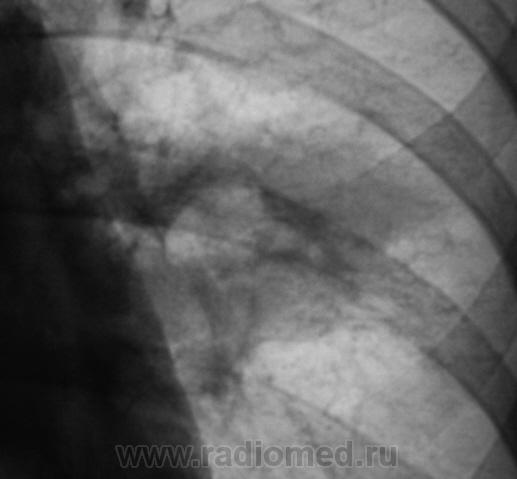

Но, эта часть "семейного клана" приехала с "момой", женой почившего в 2009 году. Мама, как "Контактная" две недели тому была направлена на цифровую флюорографию, которая была ей и произведена.

На флюшке, вроде-бы все в полном ажуре, и только справа в косто-диафрагмальном синусе незначительное количество жидкости, а так - "все в высшей степени достойно".

И где-то, чисто интуитивно, почувствовав недоверие к "маме" решили "разрезать".

Срезы "мамы".